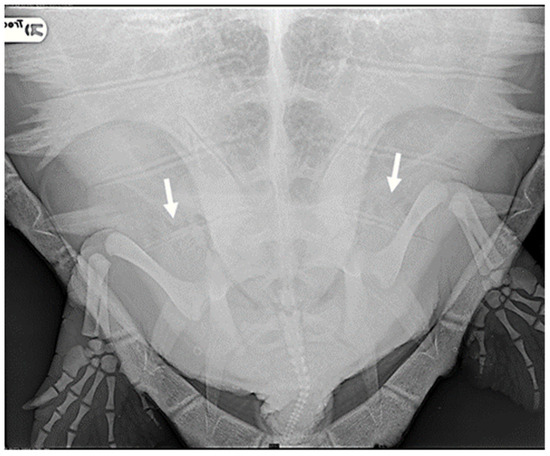

Based on the results of radiographic investigations aimed at detecting signs of GE, the turtles were categorized into groups according to the presence and extent of gas observed in the examined anatomical regions [5].

Specifically, eight animals were classified as negative (27.6%): they exhibited no radiographic signs of gas presence in any of the considered districts. In the case of 11 turtles, gas was observed in only a few anatomical areas, primarily in the marginal-costal vessels and/or renal vessels, leading to their classification as mild cases (37.9%) (Figure 1).

Figure 1.

R-ray examination in DV projection of a loggerhead turtle affected by mild GE. It is possible to detect a small amount of gas within the renal vessels (indicated by white arrows).